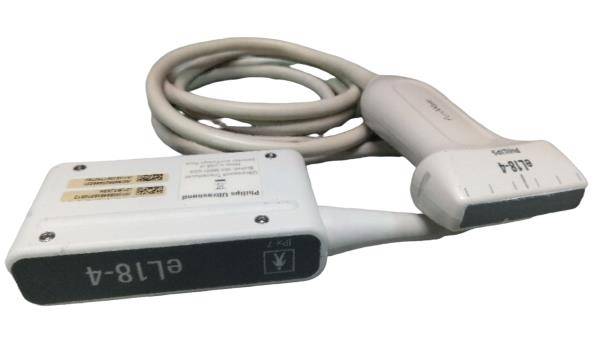

Understanding the Ultrasound Probe SIEMENS Acuson 4C1

The Ultrasound probe SIEMENS Acuson 4C1 employs cutting-edge imaging technology to provide high-resolution images that enhance diagnostic capabilities. It uses a linear array transducer, which allows it to capture detailed anatomical structures in real-time. This technology improves the clarity of the images, making it easier for healthcare professionals to identify and assess various conditions. Because of its advanced features, this probe is indispensable in ultrasound examinations.

The SIEMENS Acuson 4C1 is designed with ease of use in mind. It features an ergonomic design that allows for comfortable handling during procedures. Additionally, the probe connects seamlessly to SIEMENS ultrasound systems, ensuring smooth operation. This compatibility streamlines workflow in a clinical setting, as healthcare providers can easily transition between different imaging tasks. Therefore, its user-friendly nature contributes to efficiency in the medical workplace.